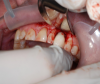

These data were used to fabricate the surgical guide and a temporary. Figure 9 shows the implant in place digitally. All the data and models were taken into account before surgery. The clinician received a 3D-printed model with the tooth extracted, a guide (Figure 10), and a healing cap and temporary (Figure 11). The latter two were required for initial stability of the implant to immediately provisionalize. The "bail-out clause" is the healing cap because if the implant cannot be immediately loaded, the healing cap can be placed instead. For this case, the patient's tooth was extracted and bone had been grafted several months previously. Figure 12 shows the patient's previous tooth bonded into place. The flap was laid (Figure 13) and the surgeon was given a set of instructions that come with every guided case.

Fig 13. The location was prepared by laying a flap.

Figure 13